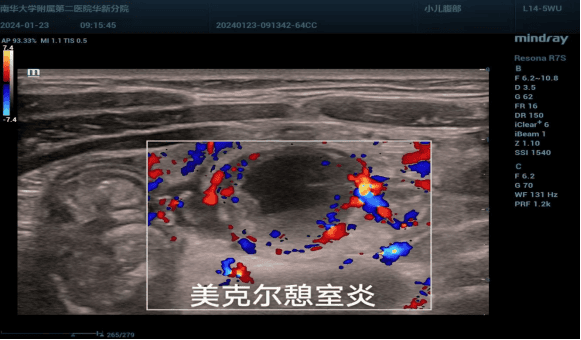

7、小儿亚专业组

主要疾病诊断包括:小儿髋关节发育不良、新生儿颅脑超声、新生儿肺部超声、肠系膜淋巴结、婴幼儿先心病、肠梗阻、肠套叠、肠旋转不良、幽门肥厚性狭窄、脑出血、斜颈等。